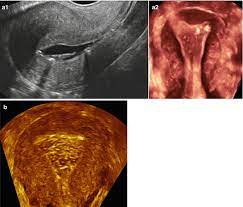

They may have a large flat base (sessile) or be attached to the uterus by an elongated pedicle (pedunculated). Uterine polyps, also called endometrial polyps, are small, soft growths on the inside of a woman's uterus, or womb. They may have a large flat base (sessile) or be attached to the uterus by an elongated pedicle (pedunculated). More information on how to use the online browser is available in the help. Endometrial polyp in an aged rhesus macaque, macaca mulatta.

Endometrial blight inspection moreover analysis. This lining grows and shrinks during different stages of the menstrual cycle. More information on how to use the online browser is available in the help. Transcervical reseksjon av endometriereseksjon hos postmenopausale kvinner. Menometrorrhagia, endometrial polyp, follicular cysts of left ovary. They come from the tissue that lines the uterus, called the endometrium. In asymptomatic women, endometrial polyps may regress spontaneously, in symptomatic women endometrial polyps can be treated safely and efficiently with hysteroscopic excision. Endometrial polyps are overgrowths of endometrial glands that typically protrude into the uterine cavity. An endometrial polyp or uterine polyp is a mass in the inner lining of the uterus. They may have a large flat base (sessile) or be attached to the uterus by an elongated pedicle (pedunculated). 68.22 incision or excision of congenital septum of uterus. A subtotal abdominal hysterectomy (salvaging the cervix) with bilateral. Are you looking for endometrial polyp icd 10 code?

International statistical classification of diseases and related health problems 10th revision. They may have a large flat base (sessile) or be attached to the uterus by an elongated pedicle (pedunculated). They can range in size from as small as a sesame seed to as big as a golf ball. They can often be suggested on u. The diagnoses for this patient are: Endometrial polyps are rare among women younger than 20 years of age. They may have a large flat base (sessile) or be attached to the uterus by an elongated pedicle (pedunculated). In asymptomatic women, endometrial polyps may regress spontaneously, in symptomatic women endometrial polyps can be treated safely and efficiently with hysteroscopic excision. Polypoid endometrial hyperplasia ( n85.0. Endometrial polyps can either be sessile or pedunculated. Endometrial polyps, which are sessile or pedunculated projections of the endometrium, develop as solitary or multiple soft tumors, which are usually stromal but in some cases composed of hyperplastic endometrium figure 10.15. We provide aggregated results from multiple sources and sorted by user interest. You can always come back for endometrial polyp icd 10 code because we update all the latest coupons and special deals weekly.

Polypoid endometrial hyperplasia ( n85.0. International statistical classification of diseases and related health problems 10th revision. Transcervical reseksjon av endometriereseksjon hos postmenopausale kvinner. Are you looking for endometrial polyp icd 10 code? They can often be suggested on u. Endometrial polyps are overgrowths of endometrial glands that typically protrude into the uterine cavity. Endometrial polyps can either be sessile or pedunculated. Pedunculated polyps are more common than sessile ones.